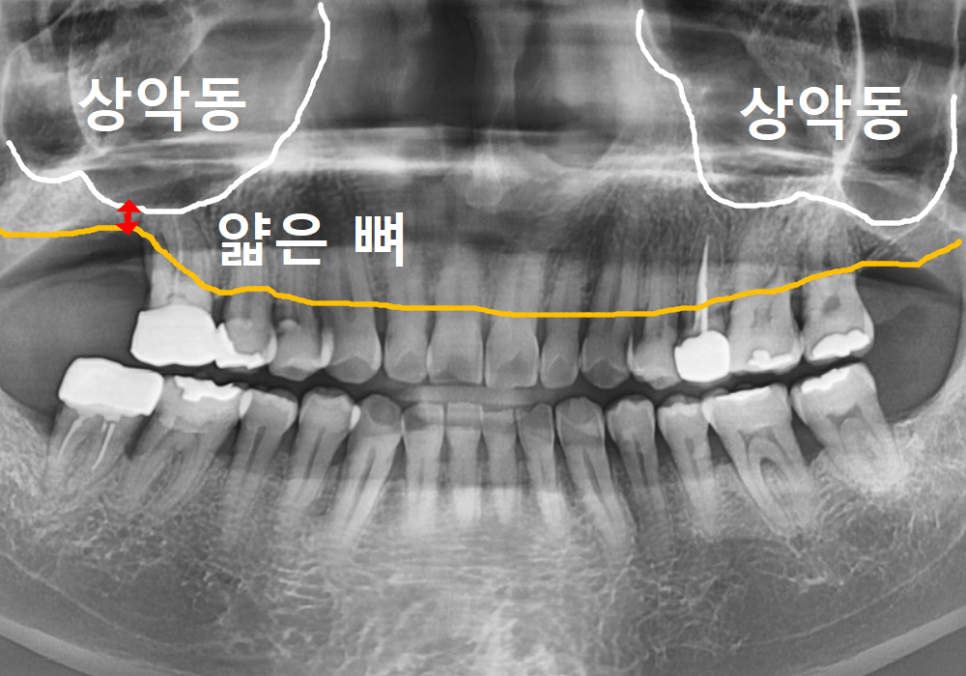

다만, 오랜 염증으로

뼈 상태가 좋지 않아 바로 심기보다는

뼈가 깨끗하게 안정될 때까지 기다린 후

상악동 거상술을 진행하기로 했습니다.

그래서 저희는 수술 전 정밀 CT를 통해

신경관과 상악동의 위치를 아주 꼼꼼하게 파악하고,

발치 후 뼈가 안정화된 것을 확인한 뒤,

상악동 거상술을 통한 뼈이식과 함께

임플란트를 안전하게 식립했습니다.

사진으로 봐도 뼈가 아주 예쁘게 잘 이식되었죠?

그로부터 3개월 뒤,

임플란트와 뼈가 완전히 하나가 된 것을 확인하고

지르코니아 보철을 올려 마침내 치료를 끝냈습니다.